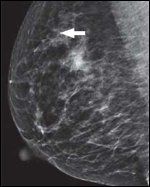

DR. NICOLE KOULANAKIS, surgical oncologist: The patient presented for baseline screening mammogram and was found to have a suspicious area of calcifications in the upper outer quadrant of her right breast (Figures 1 and 2). Stereotactic core needle biopsy revealed pleomorphic lobular carcinoma in situ (LCIS). Her history and physical exam were unremarkable. Family history was significant for two paternal cousins diagnosed with breast cancer in their 50s and a paternal uncle with a “stomach cancer.” The patient underwent a follow-up stereotactic guided biopsy which revealed a 7-mm focus of ER-positive, PR-negative, HER2/neu-negative invasive pleomorphic lobular carcinoma in the setting of diffuse LCIS (Figures 3 and 4). After discussion of her treatment and future cancer-prevention options, the patient elected to undergo bilateral mastectomies, right axillary sentinel lymph node biopsy, and immediate reconstruction. The final pathology demonstrated multiple foci of LCIS present in both mastectomy specimens, and no additional invasive cancer. The sentinel lymph nodes were negative for any metastatic disease.

Mediolateral view of right breast mammogramFIGURE 3

Invasive lobular carcinomaFIGURE 4

DR. WENDY HORN: Despite its predominantly occult nature, LCIS has been shown to be associated with mammographic calcifications, and radiologic-pathologic concordance must be established after every biopsy.[3,4] Mammographic findings occur more commonly with the pleomorphic variant of LCIS, given its tendency to undergo comedo necrosis and thus form calcifications.[5] This was the case with our patient: she underwent a stereotactic biopsy for abnormal calcifications found on a screening mammogram, which led to her diagnosis of pleomorphic LCIS.